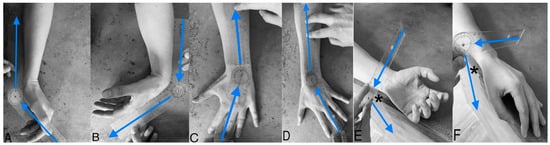

2.3. Goniometric Measurement

2.4. Grip Strength Measurement